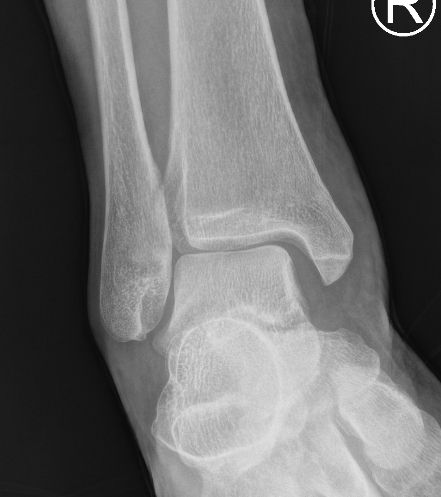

| 病徵: 四級踝關節扭傷屬於嚴重病例,韌帶斷裂,踝關節半脫位。症狀包括劇烈疼痛、腫脹、踝關節不穩定和行走困難。 |

/level4_01.jpeg) |

/level4_02.jpeg) |

| 腫痛 |

距骨移位 |